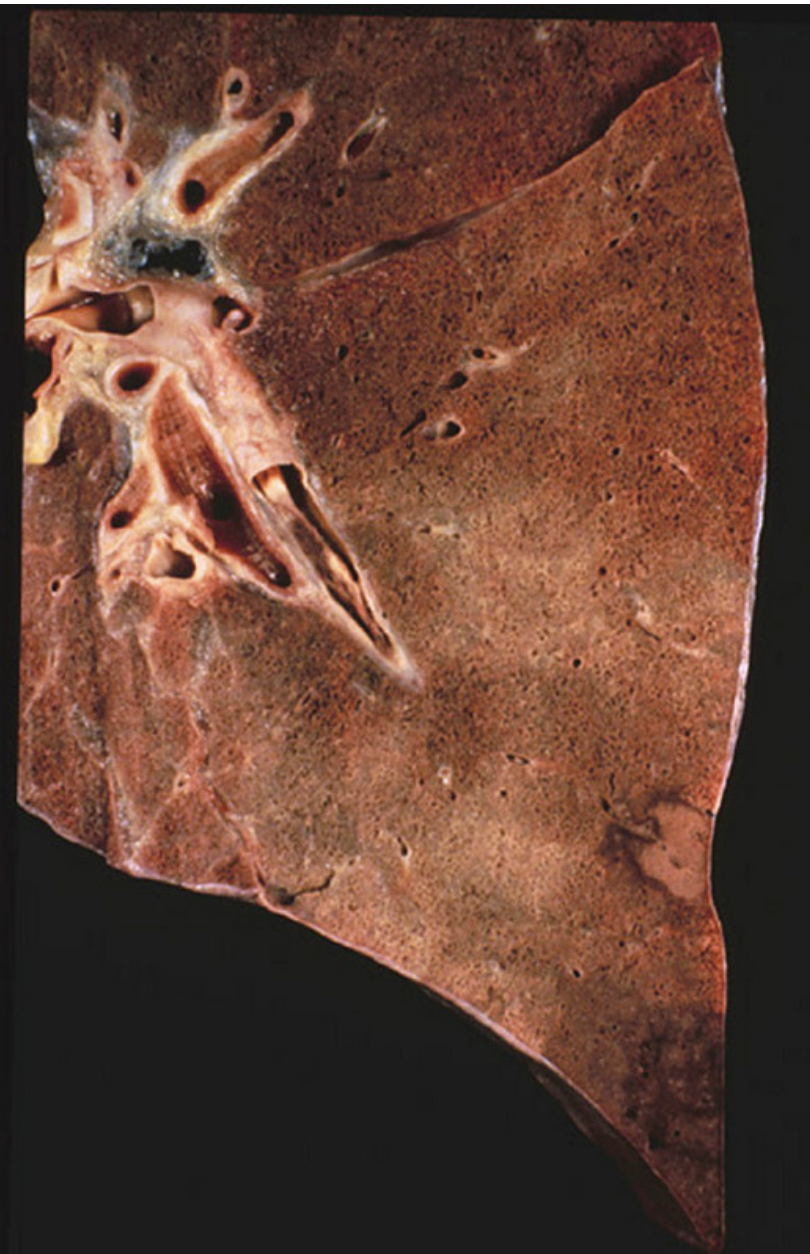

What type of necrosis of the lung parenchyma is associated with pulmonary embolism?

Coagulative necrosis. Even more, PEs lead to red infarcts. The pulmonary artery is occluded, but bronchial arteries continue to supply the affected area. If embolus resolves or infarcted tissue is reperfused, blood can flood the necrotic tissue, leading to hemorrhagic infarction. Wedge-shaped, red infarct, often pleuritic and painful.